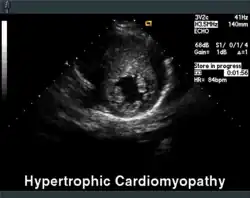

Vergrößerter linker Ventrikel im apikalen 4-Kammer-Blick -

Linker Ventrikel bei HOCM in parasternaler kurzer Achse